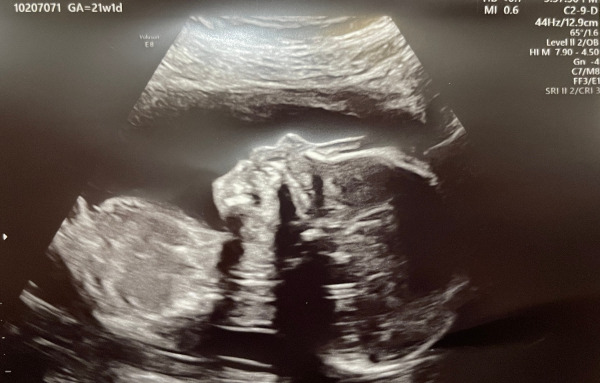

작디작은 새싹이에서 이제는 눈코입도 다 보이고, 꼬물꼬물 거리던 팔다리도 모양을 갖춰가네.

꼬물꼬물 작은 손 얼른 잡아보고 싶다~!!